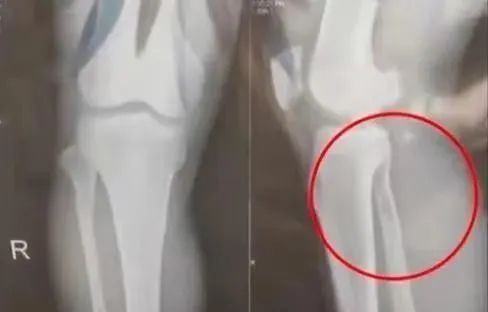

王爷爷再次举起餐桌旁的长椅,向鲁爸爸砸去,期间鲁夫人和王奶奶都在劝阻,但劝阻无效,在王爷爷的椅子即将落下时,鲁爸爸将王爷爷推向一边,爷爷当场摔倒在地,检查结果是右腿骨折。

王爷爷,腿部骨折。